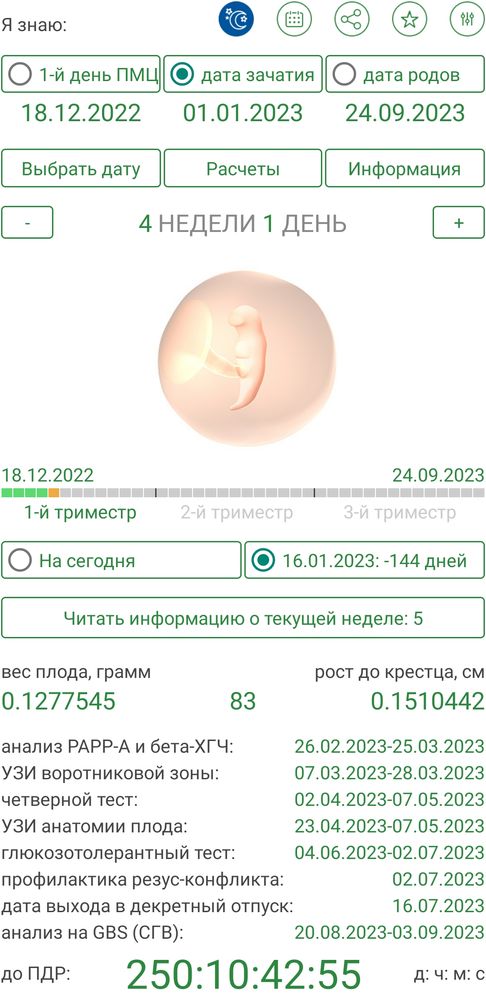

Здравствуйте, последние месячные были с 12.12.2022 по 16.12.2022, тест на беременность 9.01.23, подскажите пожалуйста, Ваше мнение, зачатие было в конце декабря допустим с 25 по 27 или 1-го января? За ранее спасибо!

Лимоночка, Но всё же Ваше мнение что это конец декабря!? А, Вы ничего не знаете об это приложение?

Gennady Babansky, Просто по нему если 1 число то всё совпадает, то что там врач сказал 4 недели и размеры вроде такие же, только почему-то первый день она смещает на 18 а не 12 декабря.

Gennady Babansky, у вас тут выбрана дата зачатия 1 января) успокойтесь, не может быть такого судя по узи. А дата родов одному богу мзвестна, можно родит в 37 недель, в 41 или вообще в 32, это не зависит от дня зачатия.

Лимоночка, Я Вас понимаю что размер ПЯ соответствует определённому сроку, который соответствует 5 неделям беременности акушерский ? Или эмбриональных? Если в приложении поставить первый день последних то оно показывает что зачатие 26 декабря было, но размер ктр не соответствует тому что на узи 1,7 мм

А если поставить 1 ое то он сдвигает первый день последних на 18 декабря и размер ктр показывает 1,5 мм почти как на узи от 16 января.